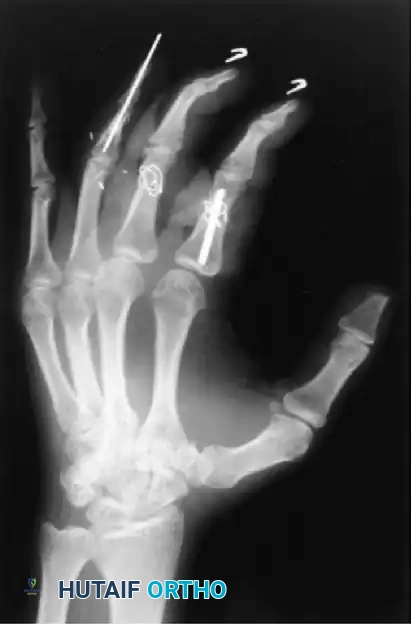

Complex Phalangeal Trauma and Replantation

In cases of severe open fractures with bone loss, structural grafting and complex pinning techniques are required. For example, in open fractures of the right hand with loss of the distal end of the middle phalanx and a painful small finger partial amputation, the proximal phalanx of the stiff small finger can be utilized as a structural graft to restore the articular column of the middle finger.

Various techniques are employed to manage middle phalangeal fractures in multiple-digit replantation. A combination of intramedullary Kirschner wire rods and wiring in the index finger, alongside intraosseous wiring alone in the middle finger, can provide excellent rotational control and stability necessary for early rehabilitation.